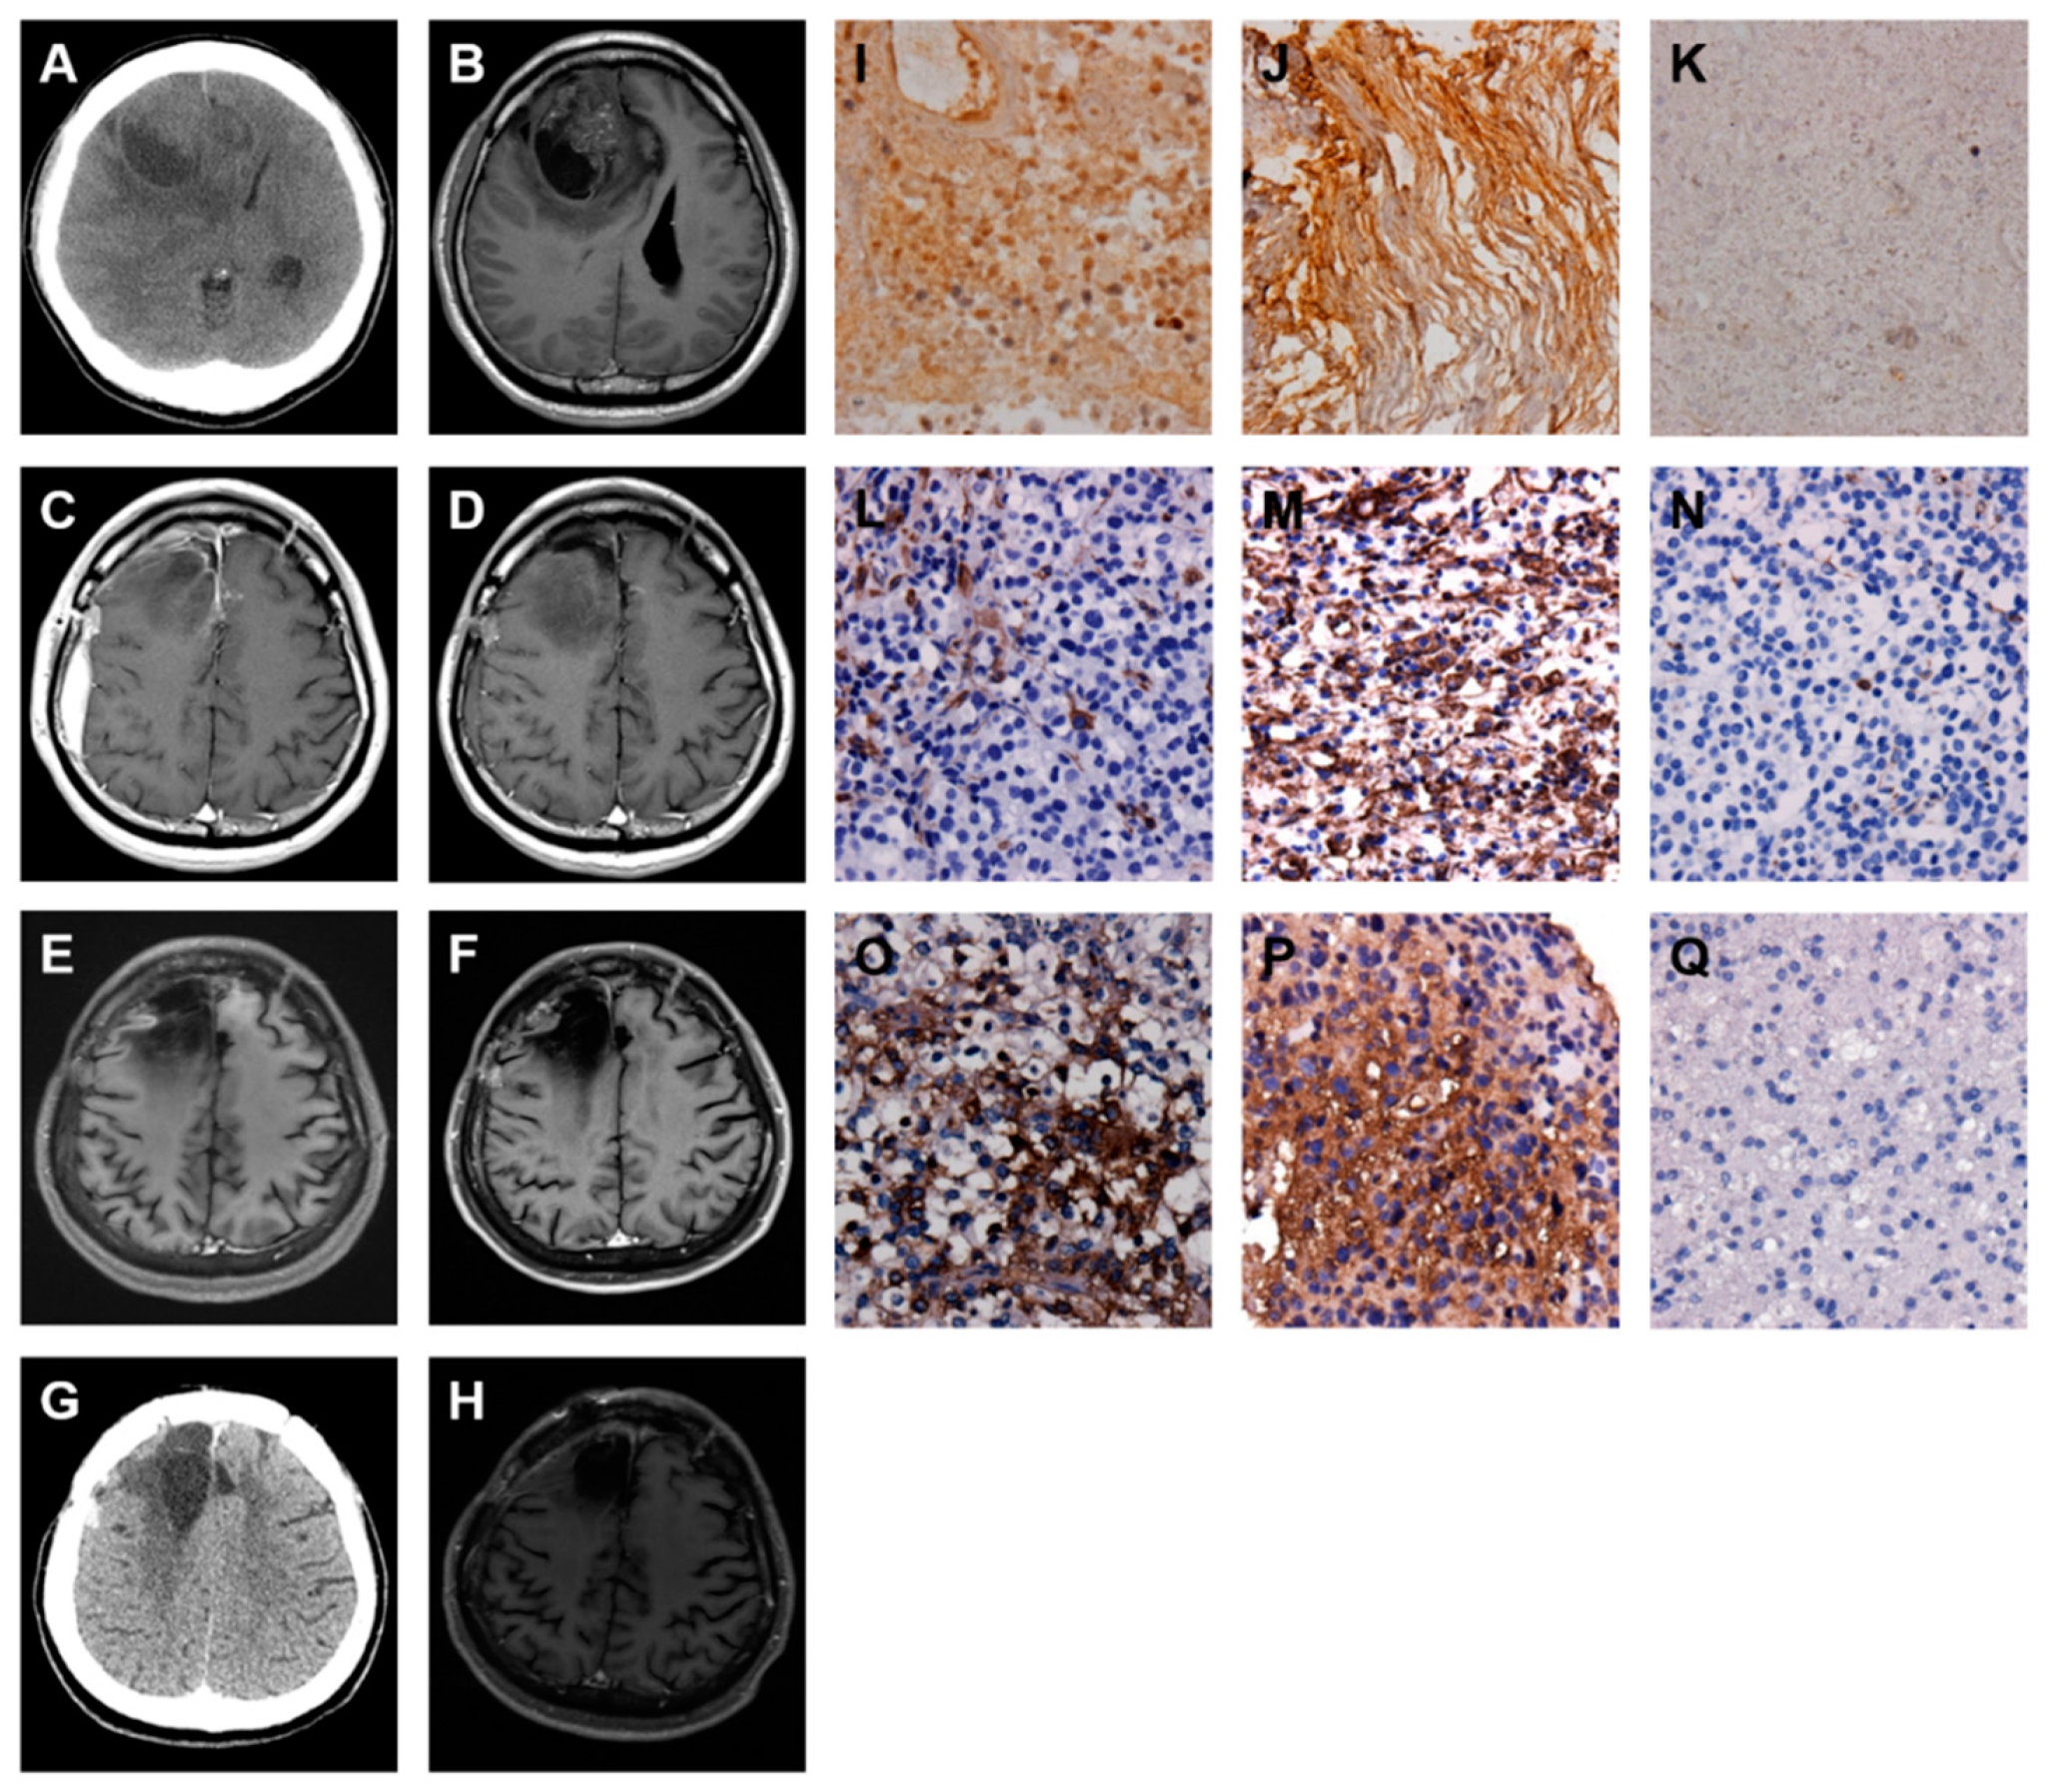

2.3. A Low-Grade Astrocytoma with Local GBM Transformation

2.4. A GBM with Local Recurrence

2.5. A GBM with Local Recurrence and Then Remote Brain Metastasis

2.6. A GBM with Spinal Metastasis

2.7. A GBM with Local Recurrence and Then Low-Grade Astrocytoma Progression

| Type | Age/Sex | 1st Surgery | 2nd Surgery | 3rd Surgery | ||||||

|---|---|---|---|---|---|---|---|---|---|---|

| Path | Date | Location | Path | Date | Location | Path | Date | Location | ||

| I | 40/F | LGA | October 2010 | R temporal | GBM | May 2013 | R temporal | |||

| II | 52/M | GBM | July 2009 | R parietal | GBM | December 2010 | R parietal | |||

| III | 44/M | GBM | August 2010 | R frontal | GBM | July 2012 | R frontal | GBM | June 2013 | R frontal |

| IV | 35/M | GBM | May 2013 | L temporal | GBM | August 2014 | T spine | |||

| V | 50/M | GBM | December 2009 | R frontal | GBM | January 2016 | R frontal | LGA | June 2016 | R frontal |

| Type | ST | 1st Surgery | 2nd Surgery | 3rd Surgery | |||||||||

|---|---|---|---|---|---|---|---|---|---|---|---|---|---|

| Path | FN * | VIM * | TGF-β | Path | FN * | VIM * | TGF-β | Path | FN * | VIM * | TGF-β | ||

| I | 36 | LGA | 1 | 2 | 2 | GBM | 2 | 3 | 3 | ||||

| II | 20 | GBM | 1 | 1 | 1 | GBM | 2 | 2 | 2 | ||||

| III | 41 | GBM | 1 | 0 | 1 | GBM | 2 | 1 | 2 | GBM | 3 | 2 | 3 |

| IV | 15 | GBM | 2 | 2 | 1 | GBM | 3 | 2 | 3 | ||||

| V | alive | GBM | 2 | 1 | 2 | GBM | 3 | 3 | 3 | LGA | 0 | 0 | 0 |